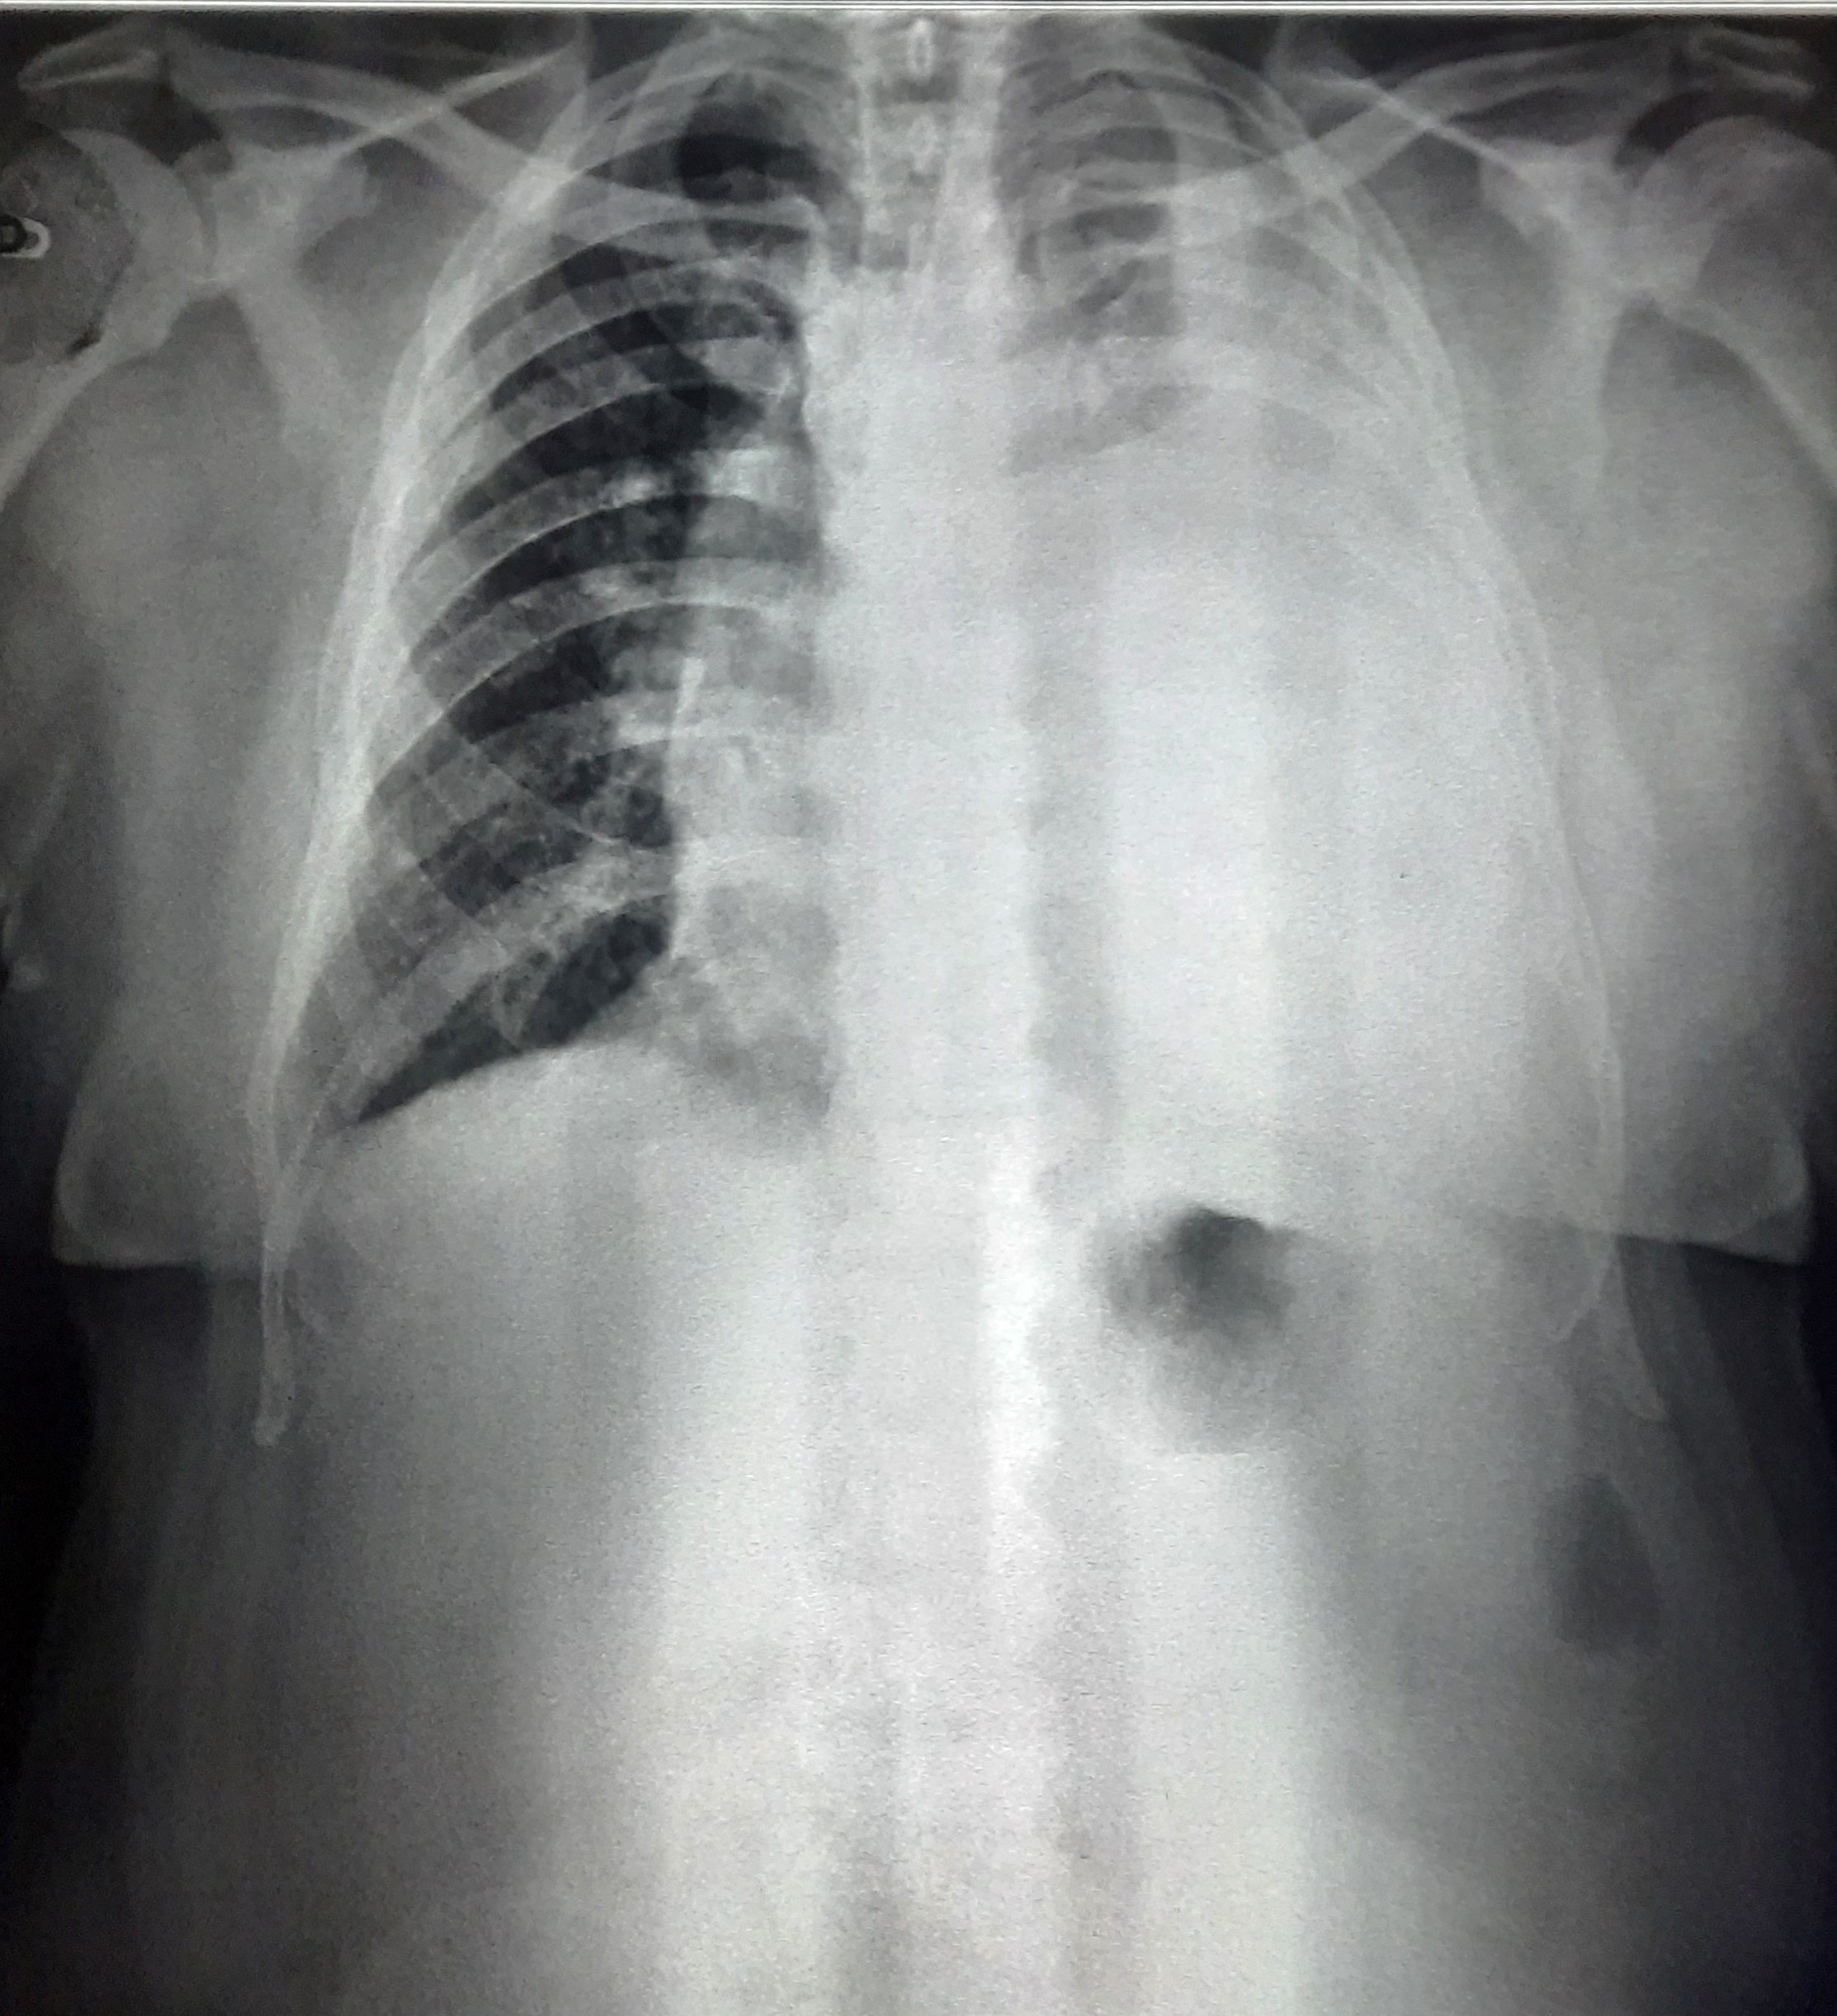

| 57 | IGGMC, Nagpur, Nagpur | P2 | 29-4415 | Saira Sayyad | Consent taken on Paper | 50 Yrs. |

Provisional Diag : Upper Respiratory Tract Infection

Final Diag : Pleural Effusion |

Non-TB Case (Confirmed) | Left CP Angle Blunting, left Mid Zone & lower Zone Homogenous Opacity Present, Left Sided Tracheal Pull, Left Lower Zone Old Calcified Lesion, Pleural Calcification? | Abnormality visible on x-ray |